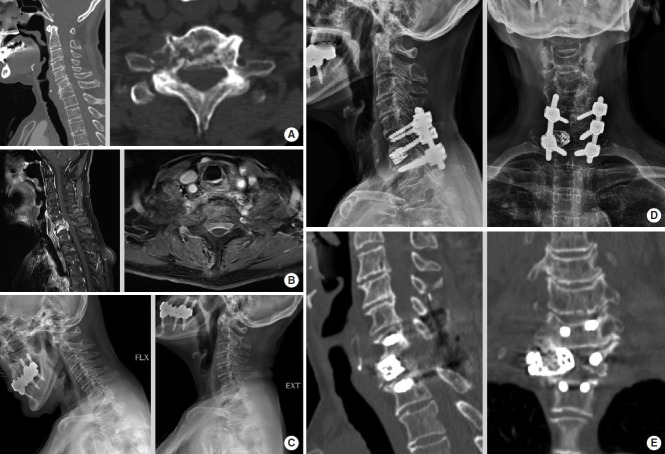

目的:本研究比较5.5 mm棒后路椎弓根螺钉固定(PPSF5.5)与前椎体切除术(AC)治疗转移性颈胸交界(CTJ)肿瘤的疗效。方法:回顾性分析2000年1月至2023年12月期间接受PPSF5.5或AC治疗的CTJ肿瘤患者。收集的数据包括人口统计学、手术细节、临床结果(颈部或背部疼痛的视觉模拟评分、脊柱不稳定肿瘤评分、McCormick评分、Nurick评分和东部肿瘤合作组评分)、放射学结果(颈椎节段Cobb角)和手术并发症(器械失败、肿瘤再生和伤口感染)。结果:AC组呈短节段融合趋势。本组患者肿瘤主要位于C7附近,一般局限于椎体。与PPSF5.5相比,AC与术后指数椎体后凸变化相关。此外,AC与较高的内固定失败发生率相关,需要翻修手术。相反,PPSF5.5组的患者往往因肿瘤再生而需要翻修手术。结论:对于CTJ转移性肿瘤,与AC相比,PPSF5.5具有更强的抗前屈性和防塌陷性,并将内固定失败率降至最低。此外,AC可能降低肿瘤复发的风险,但仅当肿瘤局限于椎体且位于CTJ上部水平时,推荐使用该方法。

Results: The AC group showed a tendency for short-level fusion. Patients in this group had tumors primarily located near C7 and generally confined to the vertebral body. AC was associated with more significant postoperative kyphotic changes in the index vertebra during follow-up than PPSF5.5. Moreover, AC was associated with a higher incidence of instrumentation failure, necessitating revision surgeries. Conversely, patients in the PPSF5.5 group tended to require revision surgery due to tumor regrowth.

Conclusion: For CTJ metastatic tumors, PPSF5.5 provides superior resistance to forward bending and collapse prevention and minimizes instrumentation failure rate compared to AC. Moreover, AC may reduce the risk of tumor recurrence, but this approach is recommended only if the tumor is confined to the vertebral body and located at the upper level of the CTJ.